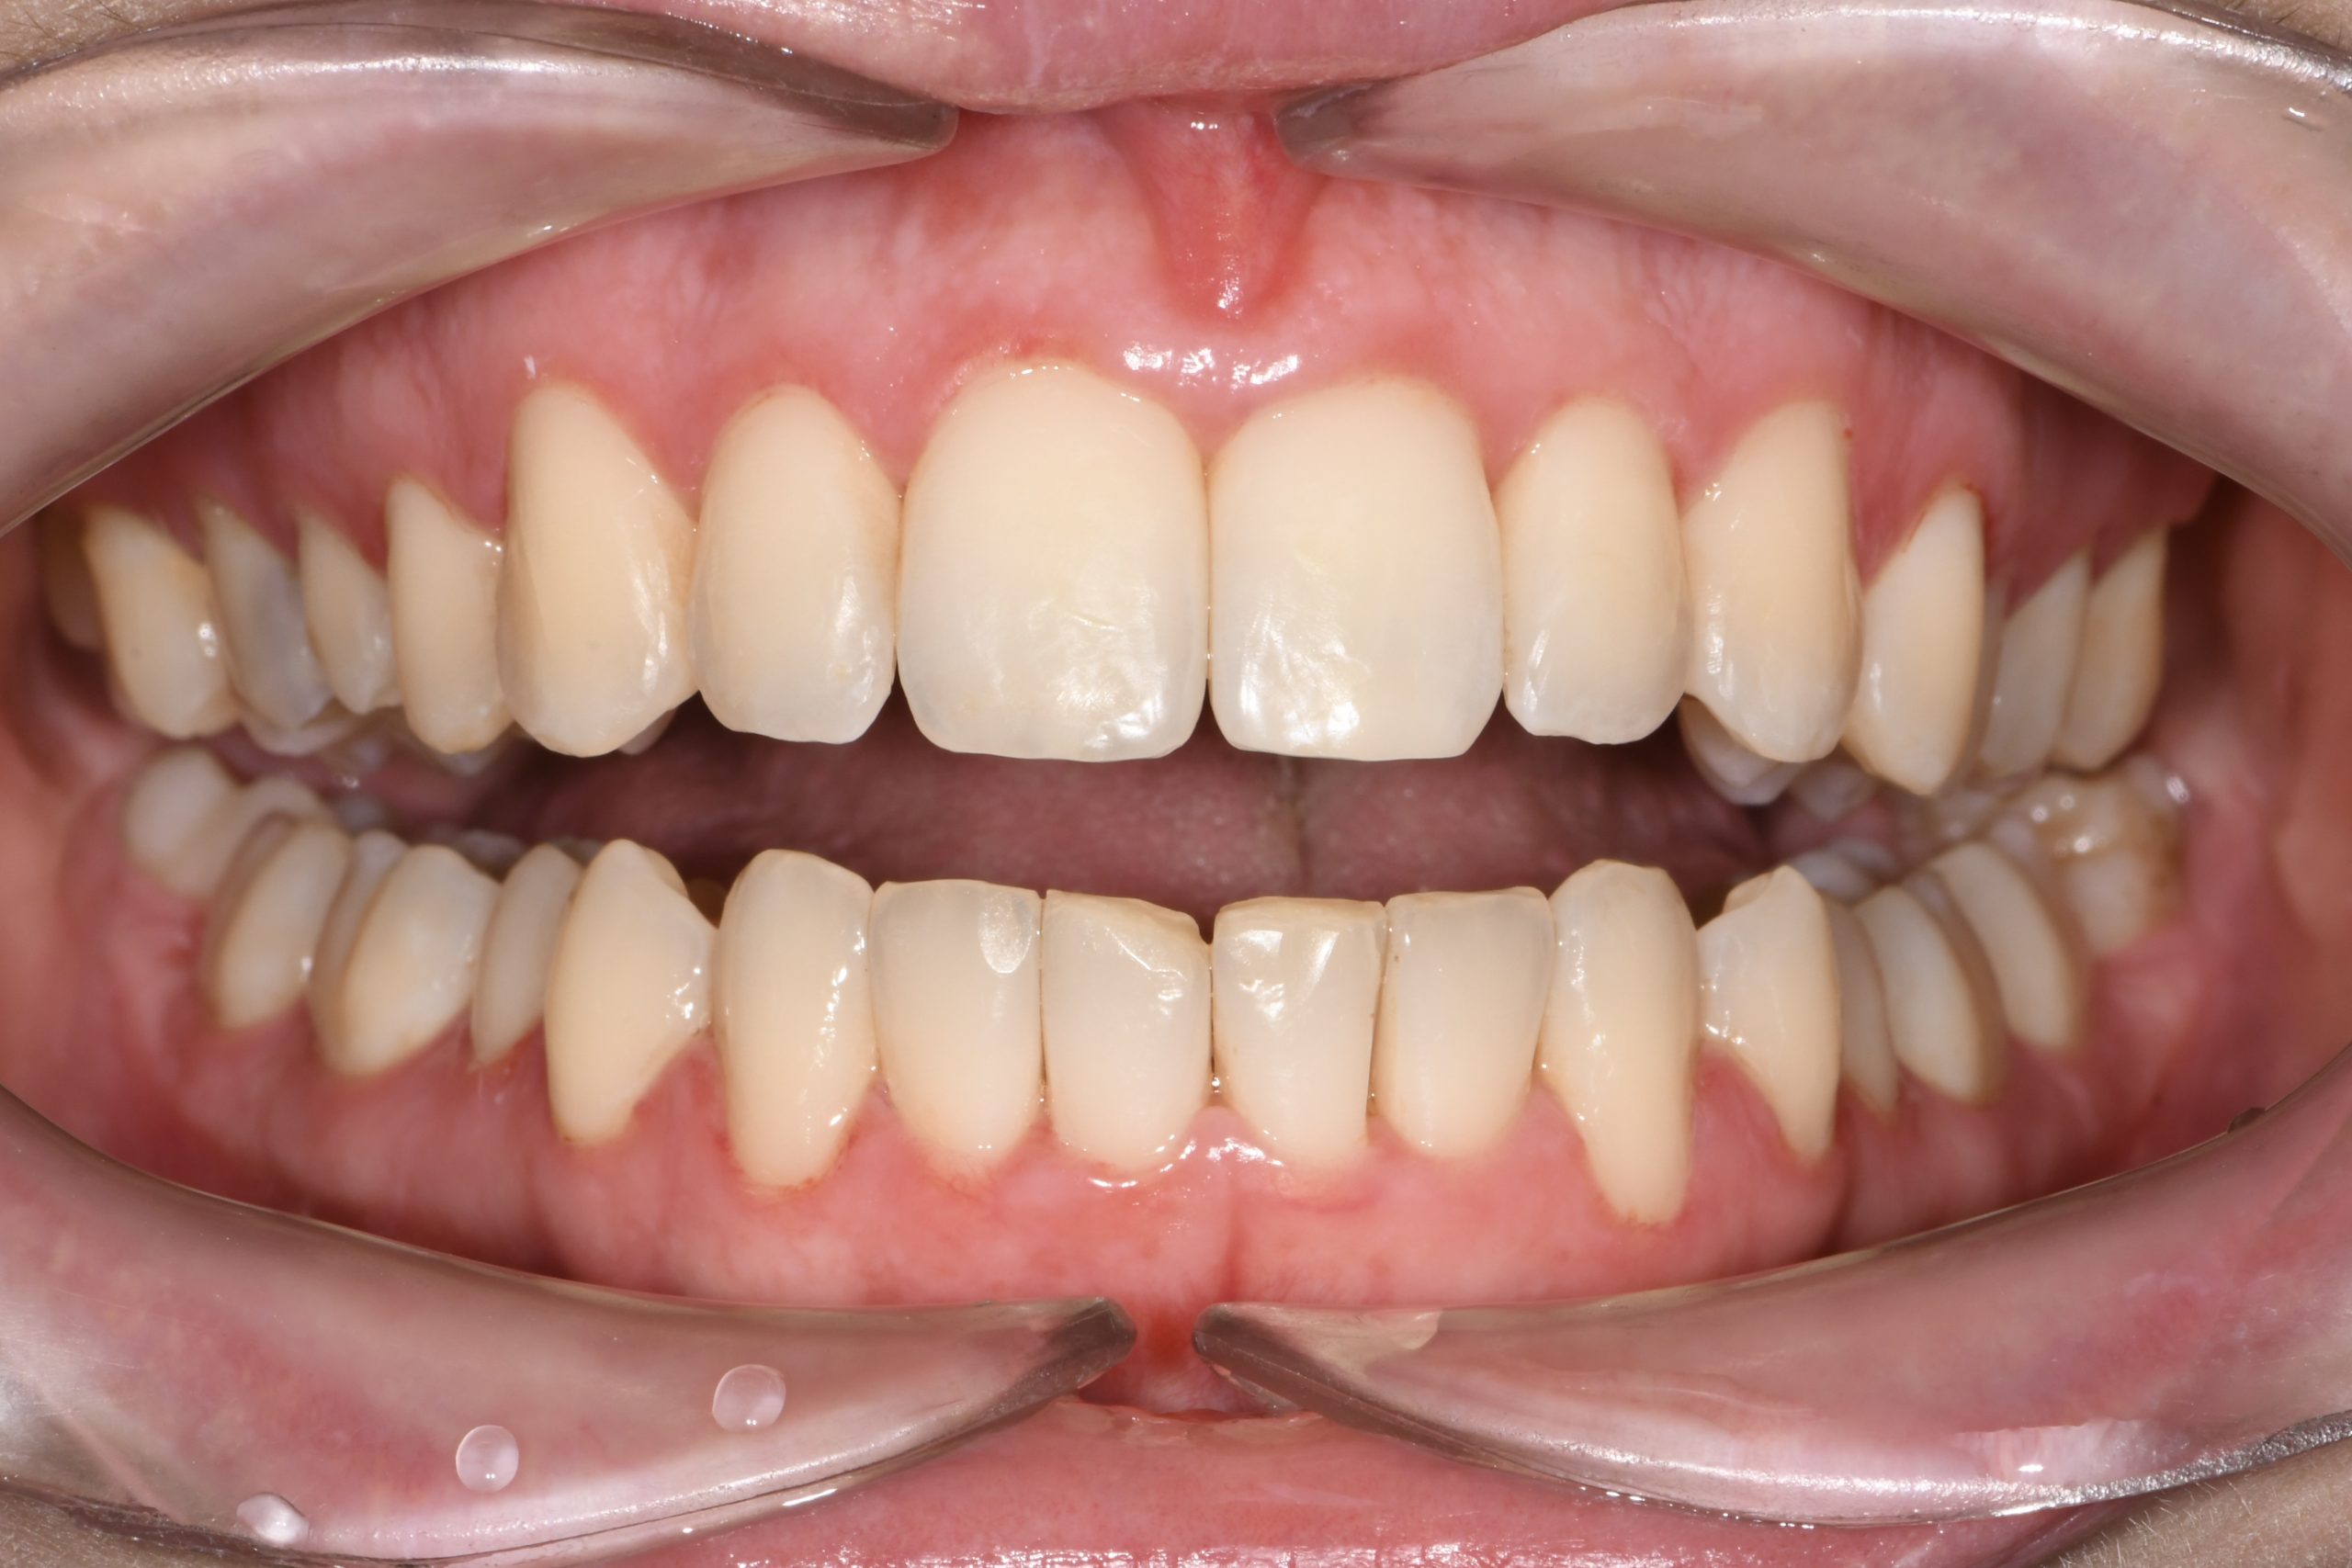

Az elmúlt évekből rengeteg szakmai referenciát tudnánk bemutatni, amelyek különböző fogszabályozási problémákat oldottak meg. Válogatva a több száz esetből, ezen az oldalon olyan képeket, információkat igyekeztünk bemutatni, amelyeknek a segítségével a jövőbeni pácienseinknek azt tudjuk üzenni: A Te fogsorod is lehet gyönyörű!

(Képeket a Pácienseink külön írásos beleegyezésével mutatjuk be!)